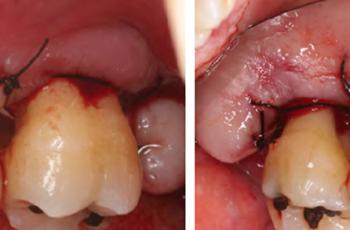

Tratamiento de un paciente con periodontitis crónica II

Presentamos un nuevo caso clínico, de un paciente con periodontitis crónica, elaborado...